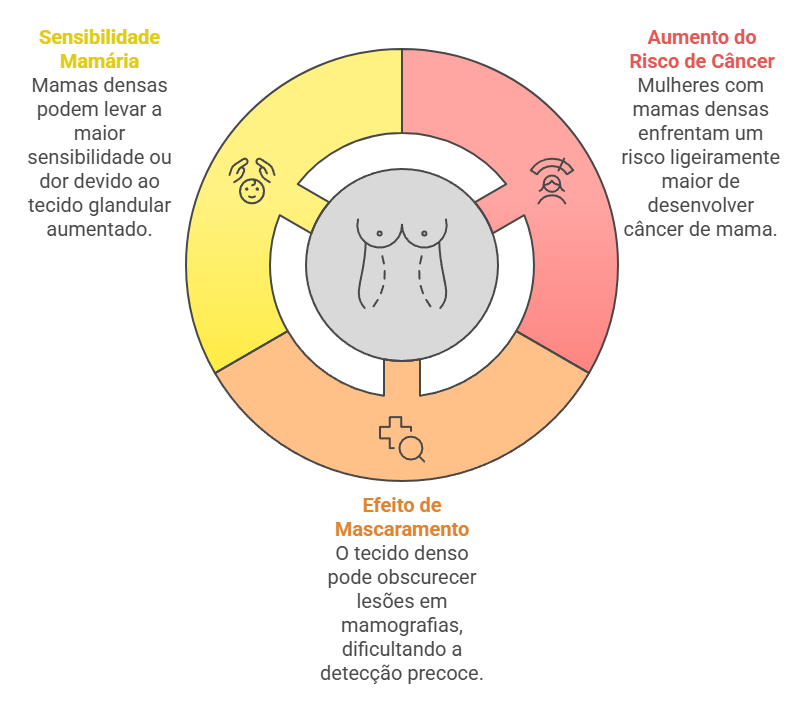

Ter mamas densas está associado a dois pontos principais de atenção:

- Aumento do Risco: Mulheres com mamas heterogeneamente ou extremamente densas (categorias C e D) têm um risco leve a moderadamente maior de desenvolver câncer de mama em comparação com mulheres com mamas adiposas. A razão exata ainda é estudada, mas acredita-se que o próprio ambiente do tecido denso possa favorecer o desenvolvimento de células anormais.

- O “Efeito de Mascaramento”: Este é o desafio mais conhecido. Como o tecido denso e um possível nódulo aparecem brancos na mamografia, a densidade pode funcionar como uma “camuflagem”, escondendo lesões em estágios iniciais. É como tentar encontrar um urso polar em uma tempestade de neve: não é impossível, mas é mais difícil.

Além disso, mamas densas podem estar associadas a maior sensibilidade ou dor mamária, justamente pela maior quantidade de tecido glandular presente.